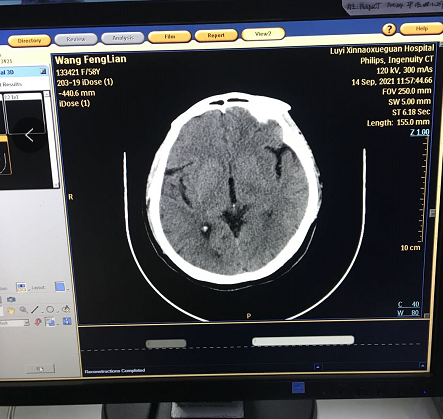

后開機測試,可以正常進入系統,做預熱正常,但是掃描時出現圖像亂碼

根據此圖像顯示問題應該在NGBP卡上,重新插拔NGBP卡,重新安裝CIRS軟件后依舊,后清理NGBP卡上小內存條,清理完成重新安裝后正常